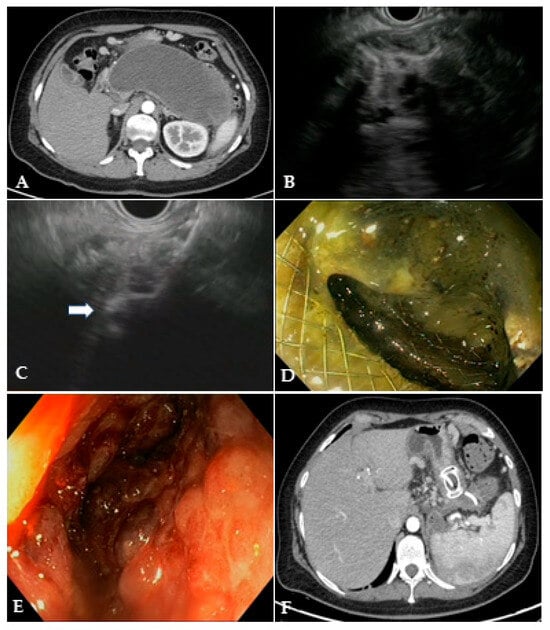

Figure 3.

(A) CT scan and (B) EUS image of a large WON with large amount of solid necrotic material; (C) EUS image of the distal flange of a 20 mm LAMS (white arrow) deployed into the WON; (D) endoscopic image through the LAMS of the necrotic cavity completely filled with necrotic debris; (E) endoscopic image of the clean cavity after drainage and repeated necrosectomy sessions; (F) CT scan image of the collapsed cavity with indwelling LAMS and a 10 French/4 cm coaxial DPS. CT: computed tomography; EUS: endoscopic ultrasound; WON: walled-off necrosis; LAMS: lumen-apposing metal stent; DPS: double-pigtail stent.